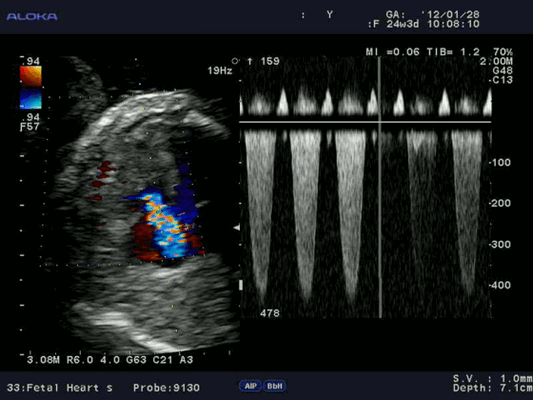

- Цветовая допплерография, при которой потоки, направленные в сторону датчика и от него, отображаются на экране различными цветами (в гамме соответственно от красного до синего). При этом зона ускорения кровотока представляется, по сути, количественным способом - путем отображения точек различного оттенка, что отражает наличие высокоскоростных потоков и феномена алайсинга.

Для облегчения выявления турбулентного движения (завихрений) существует порог скорости, выше которого происходит изменение цвета (во многих аппаратах это зелены). «Мозаичный» узор на участке турбулентного потока позволяет легко установить регургитацию (смену направления движения), что помогает определить степень недостаточности клапанов.